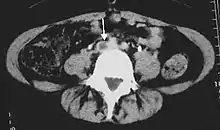

تصوير أوردة الساق

يمكن استخدام أساليب تخطيط معاوقة الامتلاء الدموي (Impedance plethysmography) وموجات دوبلر فوق الصوتية (Doppler ultrasonography) والمسح بالموجات فوق الصوتية الضاغطة لأوردة الساق، بالإضافة إلى الفحص بالدوبلكس (لتحديد مستوى تدفق الدم) للمساعدة في الكشف عن جلطة الدم وتحديد مكانها (أي إذا ما كانت أسفل الركبة أم أعلاها). وقد حل فحص دوبلكس بالموجات فوق الصوتية (Duplex Ultrasonography)، بسبب حساسيته ونوعيته وتكراريته العالية، محل تصوير الوريد بالأشعة وأصبح من أكثر طرق الاختبار المستخدمة في تقييم هذا المرض شيوعًا. ويتضمن هذا الاختبار كلاً من نظام التصوير ثنائي البعد B mode وموجات دوبلر لالتقاط صور لتدفق الدم.